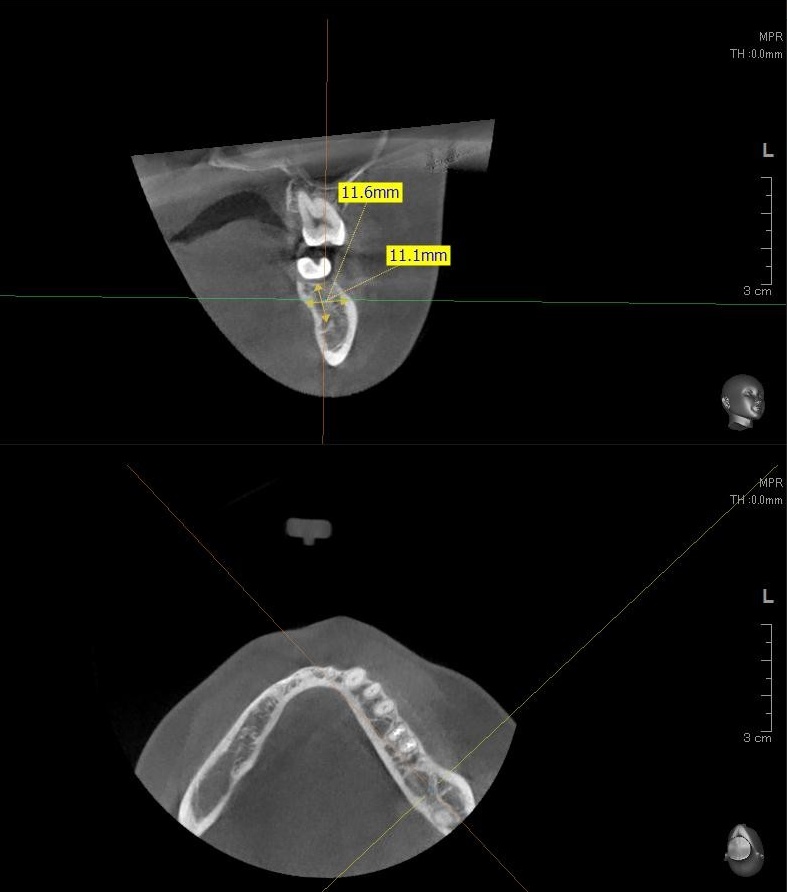

今回の患者様はインプラント植立を希望され、左下7番目の植立が決まりました。